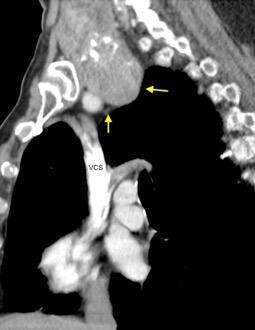

Síntomas y signos que se producen con la obstrucción total o parcial de la vena cava superior

Causas Malignas +/- 90-95%

Ca. Broncogénico (80-85%)

Linfoma No Hodgkin (15%)

Catéteres, shunts y marcapasos…23%

T. Mediastínico. Bocio

Fibrosis Idiopática

Tb, Histoplasmosis, Actinomicosis, Sarcoidosis

Carcinoma microcítico con síndrome de VCS

Grupos:

1. Obstrucción por encima de la V Ácigos. (La sangre llega al corazón a través de ella)

2. Obstrucción con participación de la V. Ácigos. (La sangre utiliza otras alternativas para llegar al corazón vía VCI).

Participación de la V. Ácigos como vía principal para llegar a la VCI.

Visible: 88%